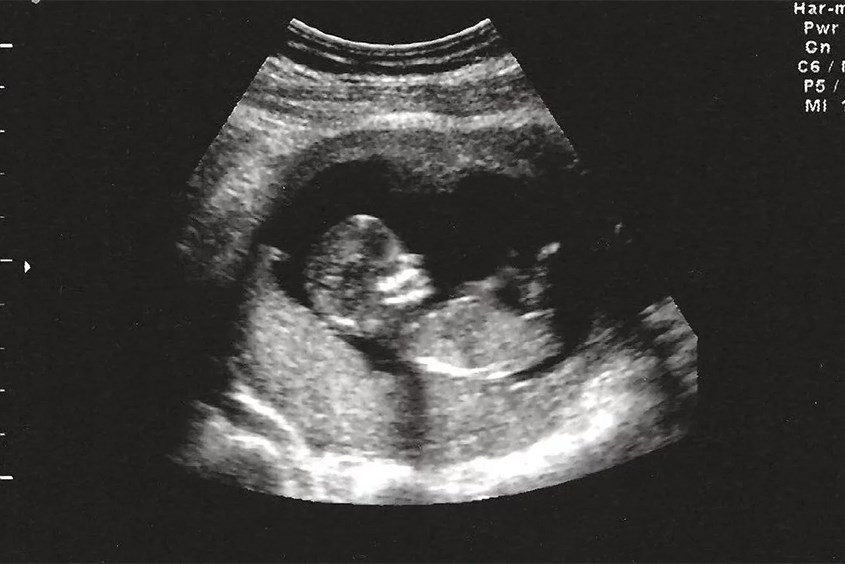

Mẹ nên tuân thủ lịch khám thai định kỳ mà bác sĩ đã chỉ định. Qua siêu âm, mẹ sẽ có cơ hội nhìn thấy hình ảnh thai nhi 15 tuần trong bụng. Việc này giúp theo dõi sức khỏe của thai nhi trong suốt thời gian mang thai. Nếu phát hiện bất kỳ dấu hiệu bất thường nào, mẹ không nên tự xử lý mà hãy đến cơ sở y tế gần nhất để được thăm khám.